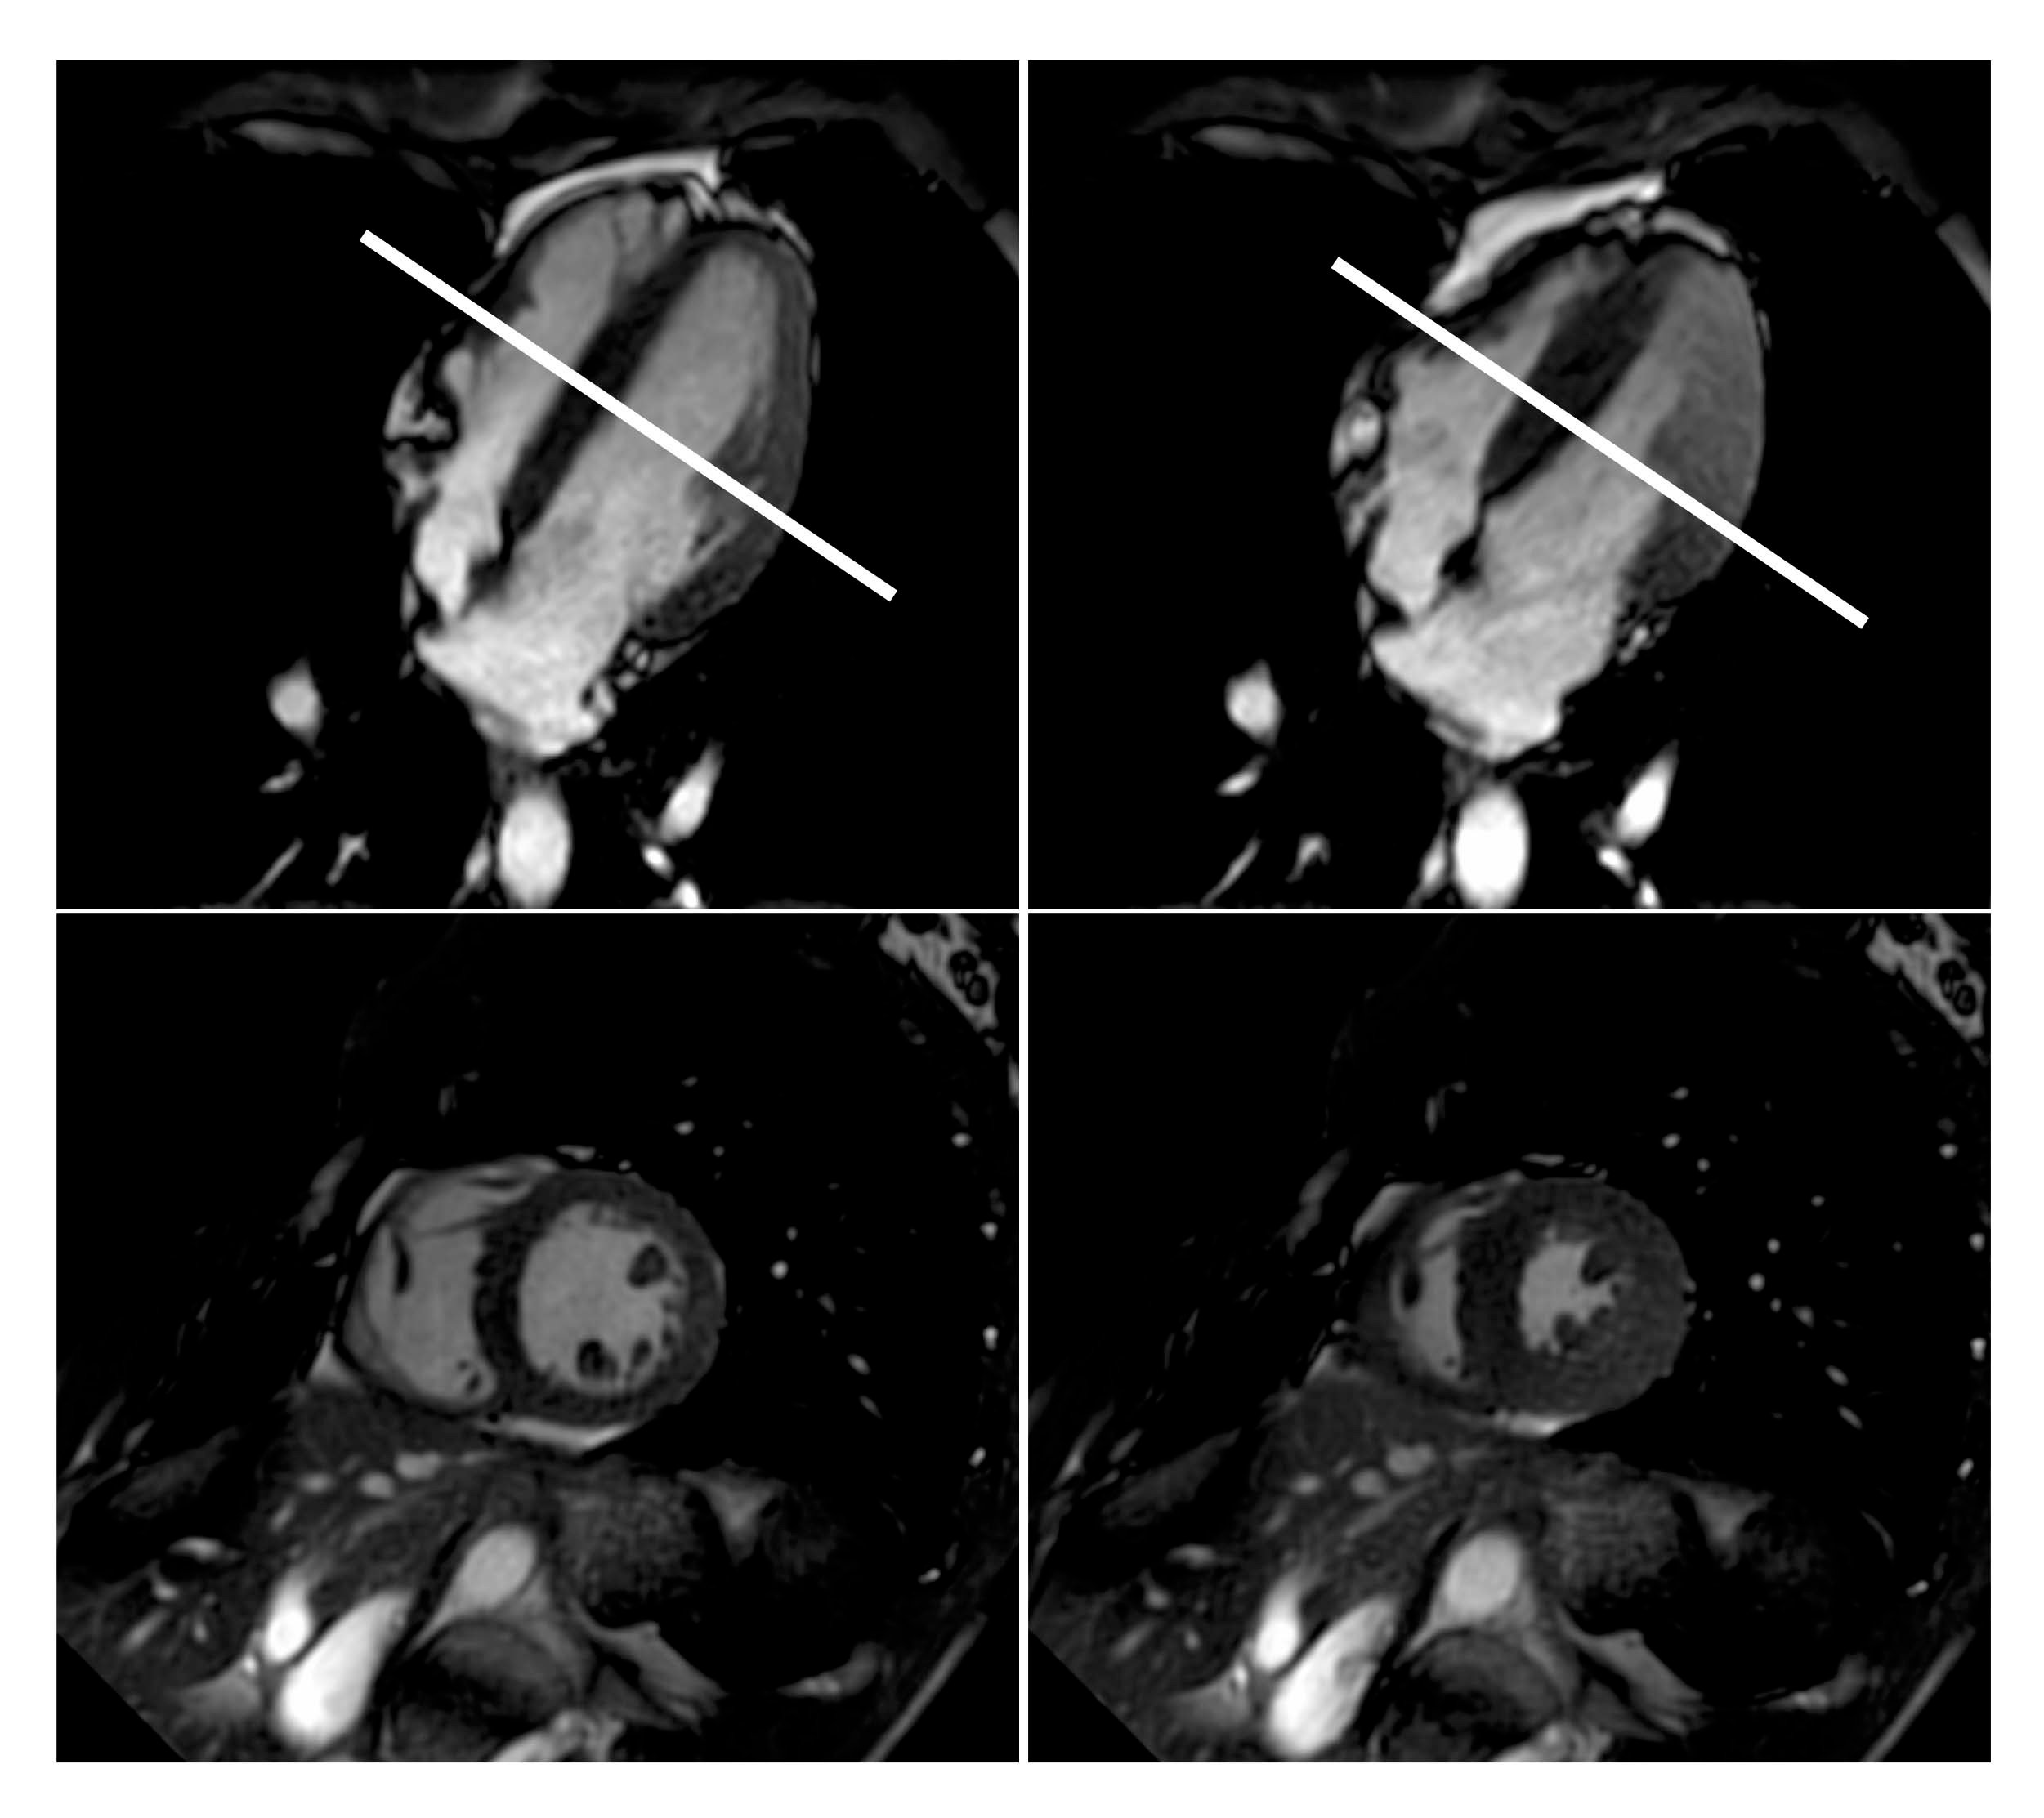

Researchers at the University of Bonn in Bonn, Germany, used MRI to study the simulated effects of free diving on the cardiovascular systems of 17 elite free divers from Germany and Austria (age range 23 to 58). To study the effects of a lack of oxygen on heart function and blood flow, respectively, the divers underwent cardiac MRI and MRI of the carotid arteries before, during and after a maximum breath hold.

The MRI exams allowed the researchers to observe the cardiovascular changes involved in the diving reflex in real time. During apnea, the amount of blood flowing to the brain through the carotid arteries increased and then leveled off.